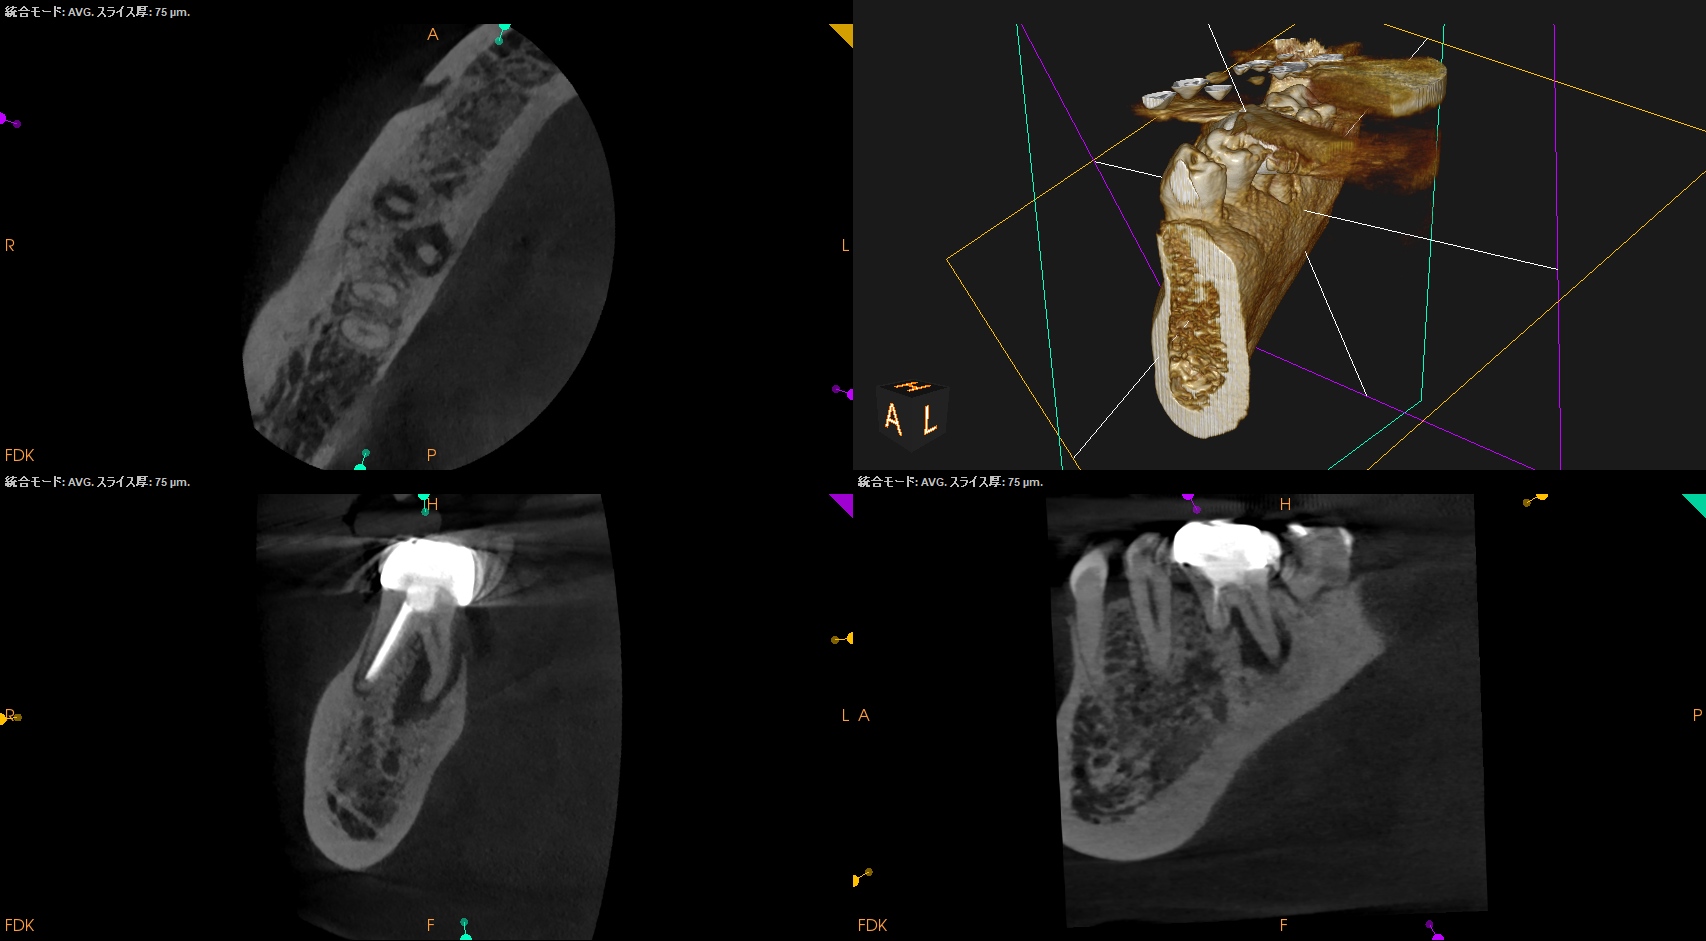

#30 Re-RCT 1yr recall(2026.3.10)

MB

ML

D

Radix

初診時と比較した。

病変は完治した。

このことから最終補綴もOKだし、経過観察も終診とさせていただいた。